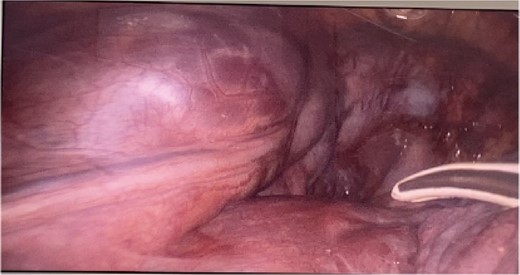

CT imaging, an anterior mediastinal mass was evident (Fig. 2), associated with the presence of thickening of interlobular septa in both lungs (Fig. 3). Surgery is carried out with diagnostic intent with suspicion of lymphoma vs DLP. A mass with cystic characteristics was found, thickening of interlobular septa and lymphatic channels that extended from the lung parenchyma to the mediastinum through the peribronchovascular space, dark serohematic pleural effusion without pleural lesions (Fig. 4).

Surgery in DLP has three objectives (Fig. 6): (i) Diagnostic surgery: The definitive diagnosis is obtained by histopathology; Minimally invasive mediastinal biopsy or thoracoscopy lung biopsy [7]. Characteristic of these is the proliferation and increase of lymphatic channels that have a connection between the mediastinum and the lungs [15]. Associated with this, hemosiderin–laden macrophages can be found adjacent to the lung parenchyma [4].